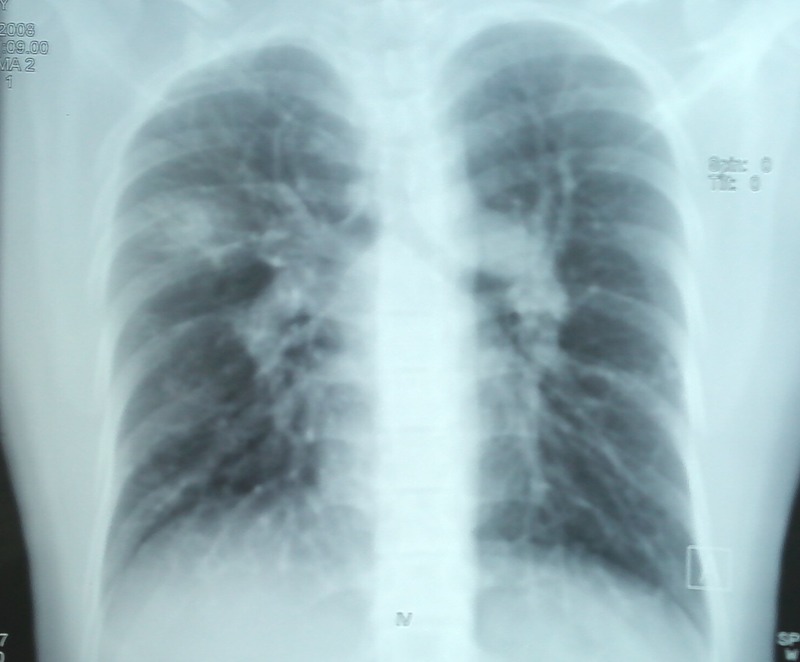

Figure 1.

Chest radiograph showing patchy alveolar opacities right upper zone and signs of pulmonary arterial hypertension.

Routine investigations revealed normal haematological, biochemical and coagulation parameters. A chest radiograph showed patchy consolidation in the right upper zone in addition to the features of PAH (figure 1). The sputum Ziehl Neelsen stain was negative for acid-fast bacilli and the tuberculin test was negative. Fibreoptic bronchoscopy showed a normal trachea-bronchial tree. Bronchoalveolar lavage yielded mildly haemorrhagic fluid which was negative for AFB, fungal and malignant cytology. Serological tests for HIV, connective tissue disorders and systemic vasculitis were negative. Two-dimensional echocardiography showed a dilated right ventricle and right atrium and moderate tricuspid regurgitation with moderate PAH (pulmonary artery systolic pressure—67 mm Hg). piral CT angiography showed a dilated main pulmonary artery due to PAH and bilateral numerous pulmonary arteriovenous malformation (PAVM) in the upper and lower lobes with an area of ground glass opacity due to pulmonary haemorrhage in the right lower lobe (figures 2–4). Ultrasonography of the abdomen, gastro-duodenoscopy and MRI brain done did not reveal any other AV malformations. Cardiac catheterisation indicated a mean pulmonary artery pressure of 54 mm Hg (72/40/54 mm Hg) and increased pulmonary vascular resistance (5.6 Wood units), with normal pulmonary capillary pressure (12 mm Hg) and an elevated cardiac index (5.5 l/min/m2). Screening of family members for AVM was negative. Genetic mutation analysis was not performed in this case due to financial constraints.